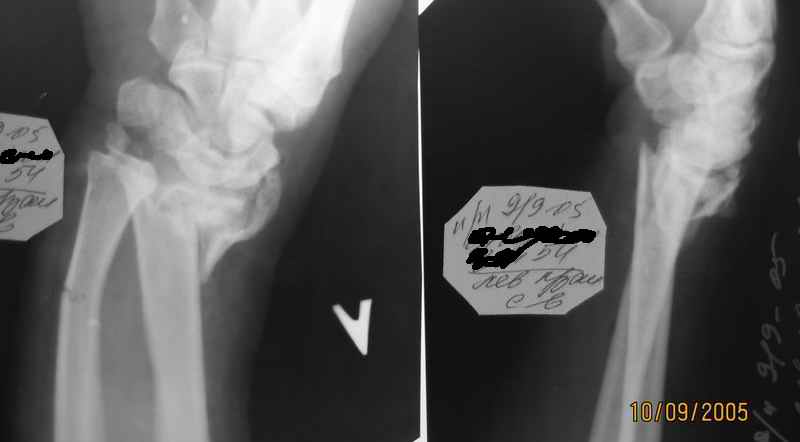

Уважаемые коллеги. Мужчина 54 года, поступил накануне-открытый перелом луча

Падение с высоты собственного роста. Перелом открытый, рана поверхностная на ладонной поверхности в проекции метэпифиза лучевой кости 1,5 см. Дежурной бригадой ПХО раны, попытка ручной репозиции, на контрольных снимках смещение остается (снимки очень низкого качества, поэтому не представляю). Какой вариант оперативного лечения лучше избрать? С уважением А. Минервин.

Абсалютное показание к внеочаговому дистракционному остеосинтезу аппаратом Илизарова за пястные кости. Судя по рентгенограмм :

Полифрактура. Откр. внутрисуставной оскольчатый перелом дистального конца лучевой кости и перелом шиловидного отростка и диафизарный перелом локтевой кости со смещением костных отломков. Для достижение идеального устранение смещений костных отломков (что очень важно для дальнейшего воостановление функции лучезапстного сустава) предлагаю по новой методики нашей клиники.

По рентген у луча "минус" вариант и это отрицательно будет высказываться на функции лечезапятсного сустава, т.е. у больного ограничение локтвеой девиации кисти.